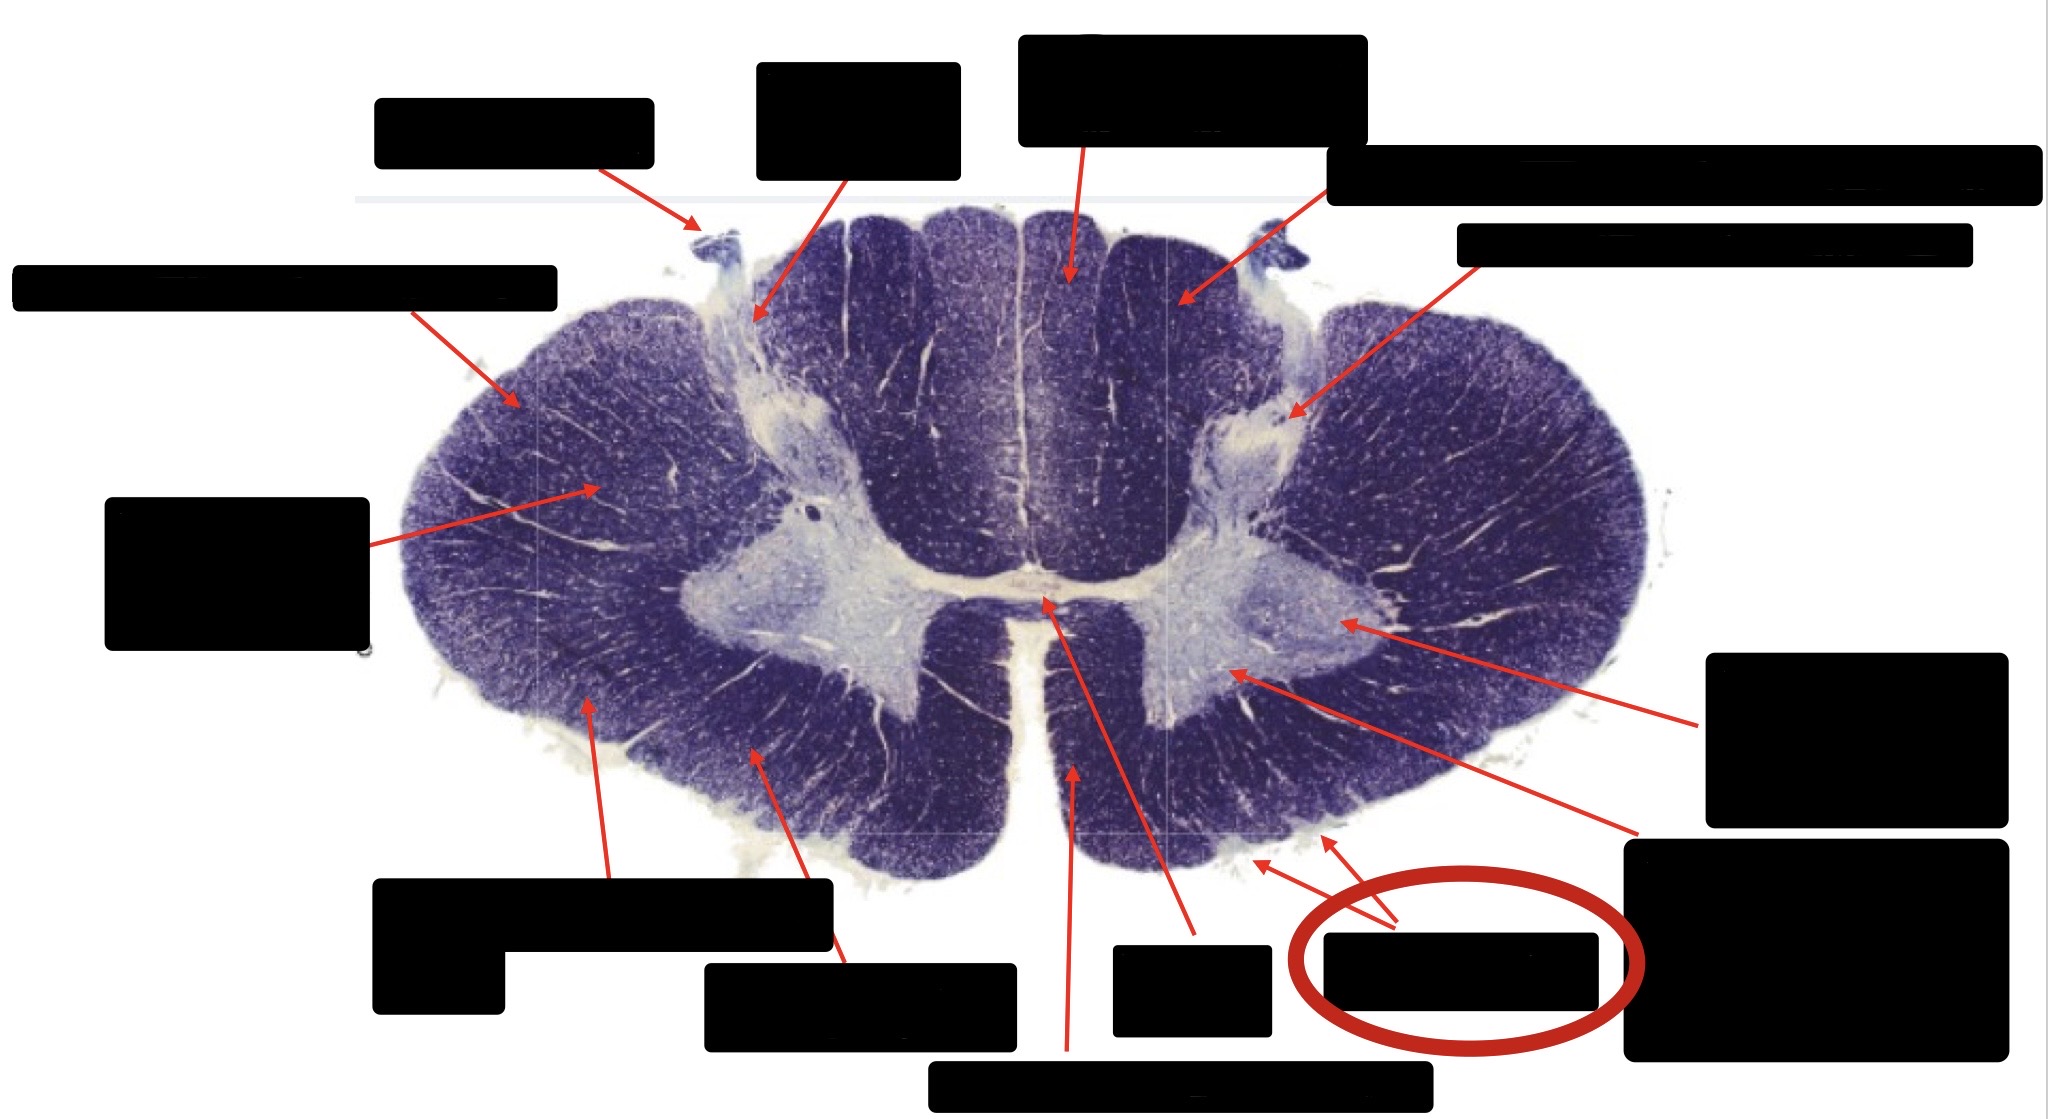

Anterior Spinal Artery

Denticulate Ligament

Ventral Root

Dorsal Root

Posterior Column Fasciculus Gracilis

Large Fiber Entry Zone

Central Canal

Dorsal Rootlet

Lissaeur’s Tract & Small Fiber Entry Zone

Substantia Gelatinosa

Lateral Corticospinal Tract

Anterior Horn Motor Neuron

Spinothalmic Tract

Anterior Horn Motor Neurons